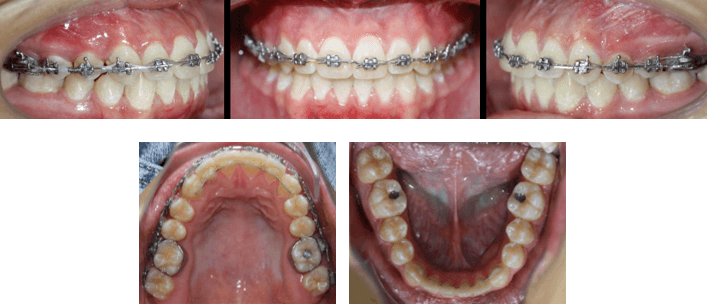

Fotografías Iniciales de Inicio de Tratamiento de Ortodoncia Prequirúrgica

Fotografías Intraorales Pre Quirúrgicas

El paciente se ha tratado bajo el concepto de Surgery First ya que se realizó la intervención quirúrgica de forma temprana con una mínima alineación y nivelación, evitando las desventajas de una larga etapa de ortodoncia prequirúrgica.